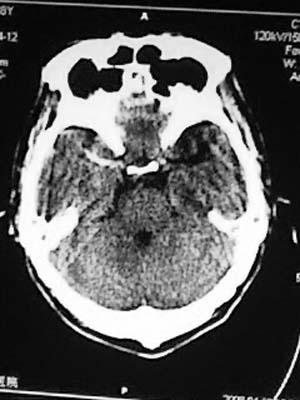

男性,67岁,上楼梯时未扶稳墙后仰摔倒,送入我院,患者诉腰痛头昏,有恶心感。

ct片如下:

枕骨骨折